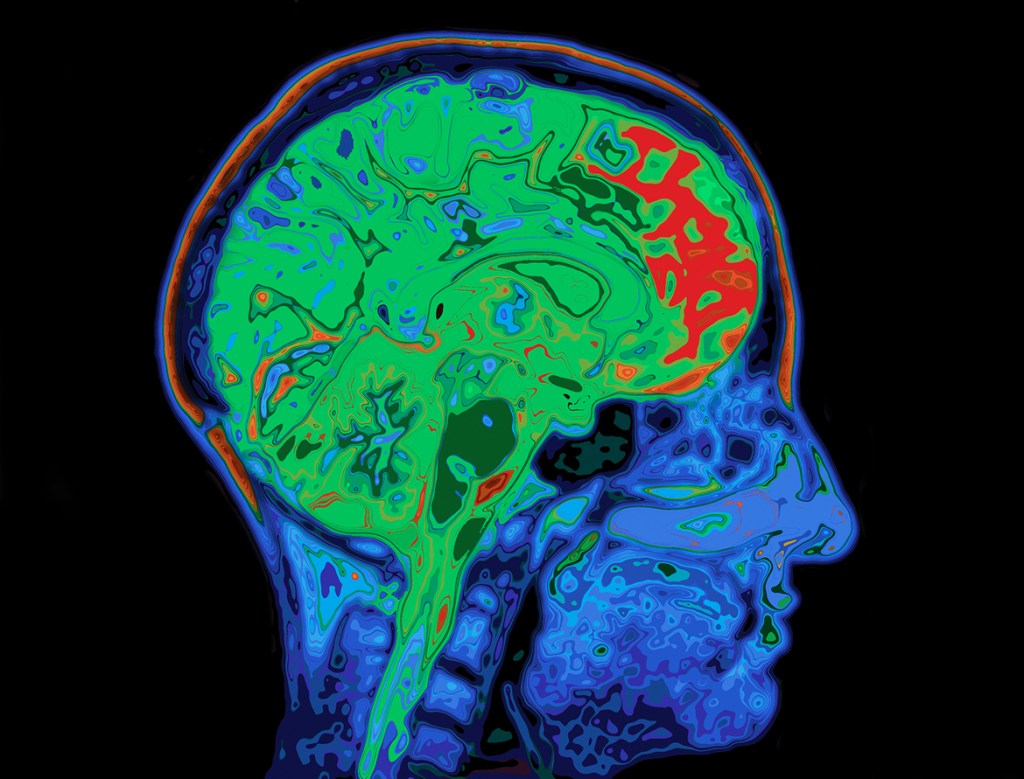

Firstly, there are key components in the brain that light up like a Christmas tree when people lie. In one study, researchers put participants in an fMRI machine (which is a large machine which allows you to see blood flow in the brain, highlighted on a screen. More blood flow means more activity which means that part of the brain is being used more heavily at any given moment).

Researchers asked participants to play a little game. They got money for winning. And, about halfway through, the system displayed some sort of “error” where it supposedly didn’t record their original answer. The participants were then given an opportunity to lie. Those who took the opportunity showed massively increased activity in some key areas that controlled higher thinking, memory and emotion.

In fact, fMRI imaging is said to be more accurate at detecting lies than traditional polygraphs (the original lie detectors from movies or the Jeremy Kyle show). Some research has suggested that combining these two techniques together could lead to incredibly accurate results in terms of telling if someone is telling the truth. They could even be combined with strategic questioning to find out concealed information.

So what parts of the brain are responsible for lying?

- Pre-frontal Cortex – this is the newest part of the brain in evolutionary terms and is responsible for complex problem-solving and for modulating our behaviour. Its role in lying seems to be twofold. On the one hand, you need to be able to come up with a good lie that’s believable. This requires some horsepower. On the other hand, you need to suppress the truth and ensure you stick to your story. Both of these are taxing.

- Amygdala – from the newest to one of the oldest parts of the brain. The amygdala is part of the system responsible for emotion. On the one hand, lying and suppressing the truth can spark feelings of guilt and panic. On the other, for a lie to be passable, it requires an emotional component.

- Temporal lobes – involved in working memory, lies often require knitting information from memory with newly fantastic and imaginary scenarios. This is tricky work. A lie about flying to Antarctica will require you to remember what it’s like there, the qualities you can recall about the peninsula, the food you ate, and the things you saw. Then you need to weave that knowledge into the lie. This is effortful and requires your working memory.

- Hippocampus – where do those memories of Antartica come from? Maybe you read about it, or perhaps you saw something on TV. All of these memories need to be accessed in order to create a proper lie, which is the role of the hippocampus. It’s the centre for long-term memory.